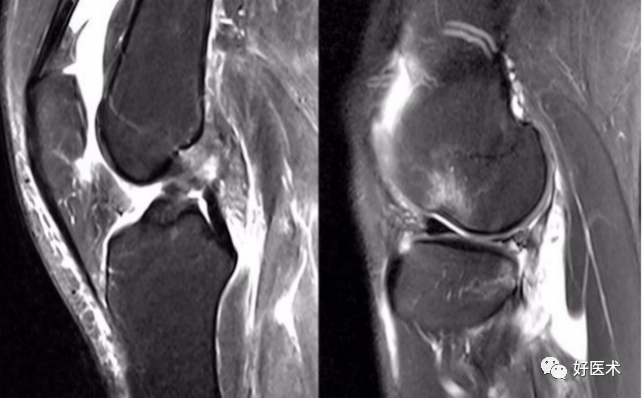

(二)ACL的正常MRI表现

各序列均为低信号。

韧带平直,边界清楚,有较好的张力。

韧带内可有脂肪及滑膜条纹影。

(七)ACL损伤直接征象

1)ACL本身的形态和信号异常:

2)不连续:

有韧带的低信号,但中断不连续。

一般见于新鲜损伤。

3)方向异常(ACL 下垂征):

有较完整的韧带低信号,但方向异常,呈下垂状。

一般见于股骨附着部的陈旧损伤,损伤的ACL下垂并粘附在PCL上。

4)消失:

髁间窝空虚,无韧带信号。

见于较久的损伤,损伤的ACL撕裂较重呈马尾状,无滑膜包裹,逐渐被关节内的酶腐蚀而消失。